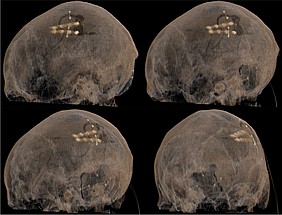

Bei bestimmten Bewegungsstörungen, die nicht oder nicht mehr ausreichend auf eine medikamentöse Therapie ansprechen, ist es möglich, die hierfür verantwortlichen Hirnareale durch die sog. Tiefe Hirnstimulation zu beeinflussen. Hierbei werden feine Elektroden in das Gehirn eingesetzt, um fehlerhafte Nervenstrukturen mit elektrischen Impulsen zu aktivieren oder zu hemmen. Beim Morbus Parkinson, dem essentiellen Tremor oder der Dystonie sind beispielsweise spezifische Hirnareale überaktiv, die dann gezielt durch die Tiefe Hirnstimulation gehemmt und die Symptome wie Zittern oder Muskelsteifigkeit dadurch unterdrückt werden können. Die Hirnregionen selbst bleiben dabei intakt, sodass die Stimulation jederzeit rückgängig gemacht werden kann. Die elektrische Stimulation wird durch einen Impulsgeber gesteuert, der ähnlich wie ein Herzschrittmacher unter die Haut an der Brust der Patient:innen implantiert wird. Die Einstellungen des Impulsgebers lassen sich von außen jederzeit verstellen, sodass die Stimulation an veränderte Bedürfnisse der Patient:innen stets angepasst werden kann.